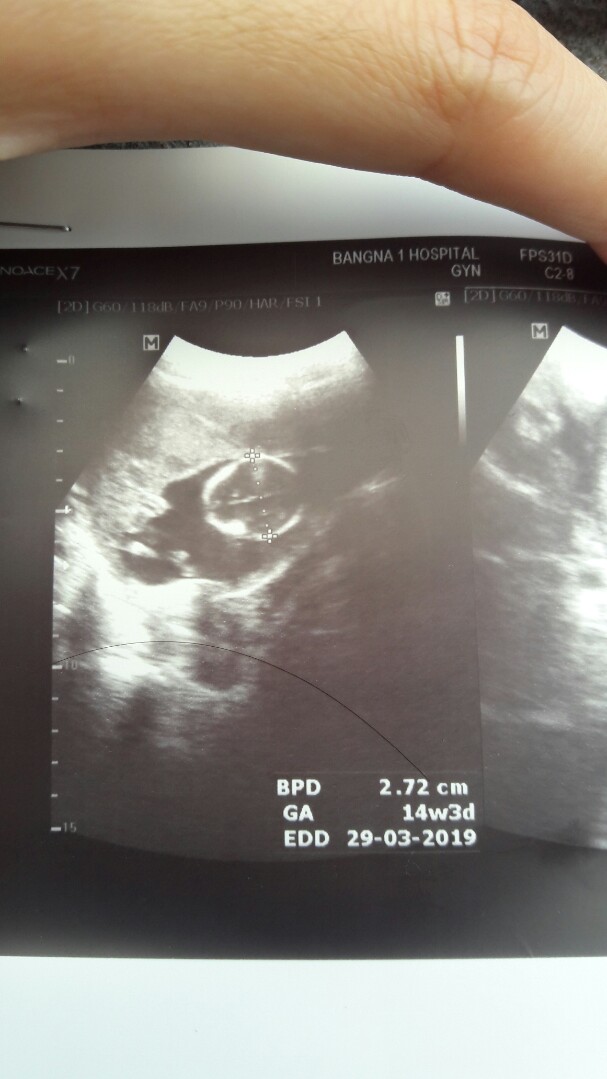

16 w ค่ะ ตอนนี้ 19 w แล้ว ใจแม่อยากคลอดแล้วค่ะ